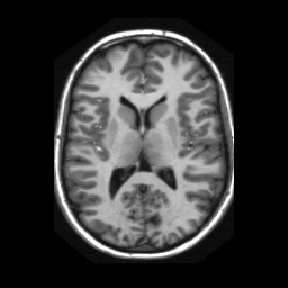

Reconstructing under-sampled k-space measurements in Compressed Sensing MRI (CS-MRI) is classically solved with regularized least-squares. Recently, deep learning has been used to amortize this optimization by training reconstruction networks on a dataset of under-sampled measurements. Here, a crucial design choice is the regularization function(s) and corresponding weight(s). In this paper, we explore a novel strategy of using a hypernetwork to generate the parameters of a separate reconstruction network as a function of the regularization weight(s), resulting in a regularization-agnostic reconstruction model. At test time, for a given under-sampled image, our model can rapidly compute reconstructions with different amounts of regularization. We analyze the variability of these reconstructions, especially in situations when the overall quality is similar. Finally, we propose and empirically demonstrate an efficient and data-driven way of maximizing reconstruction performance given limited hypernetwork capacity. Our code is publicly available at https://github.com/alanqrwang/RegAgnosticCSMRI.